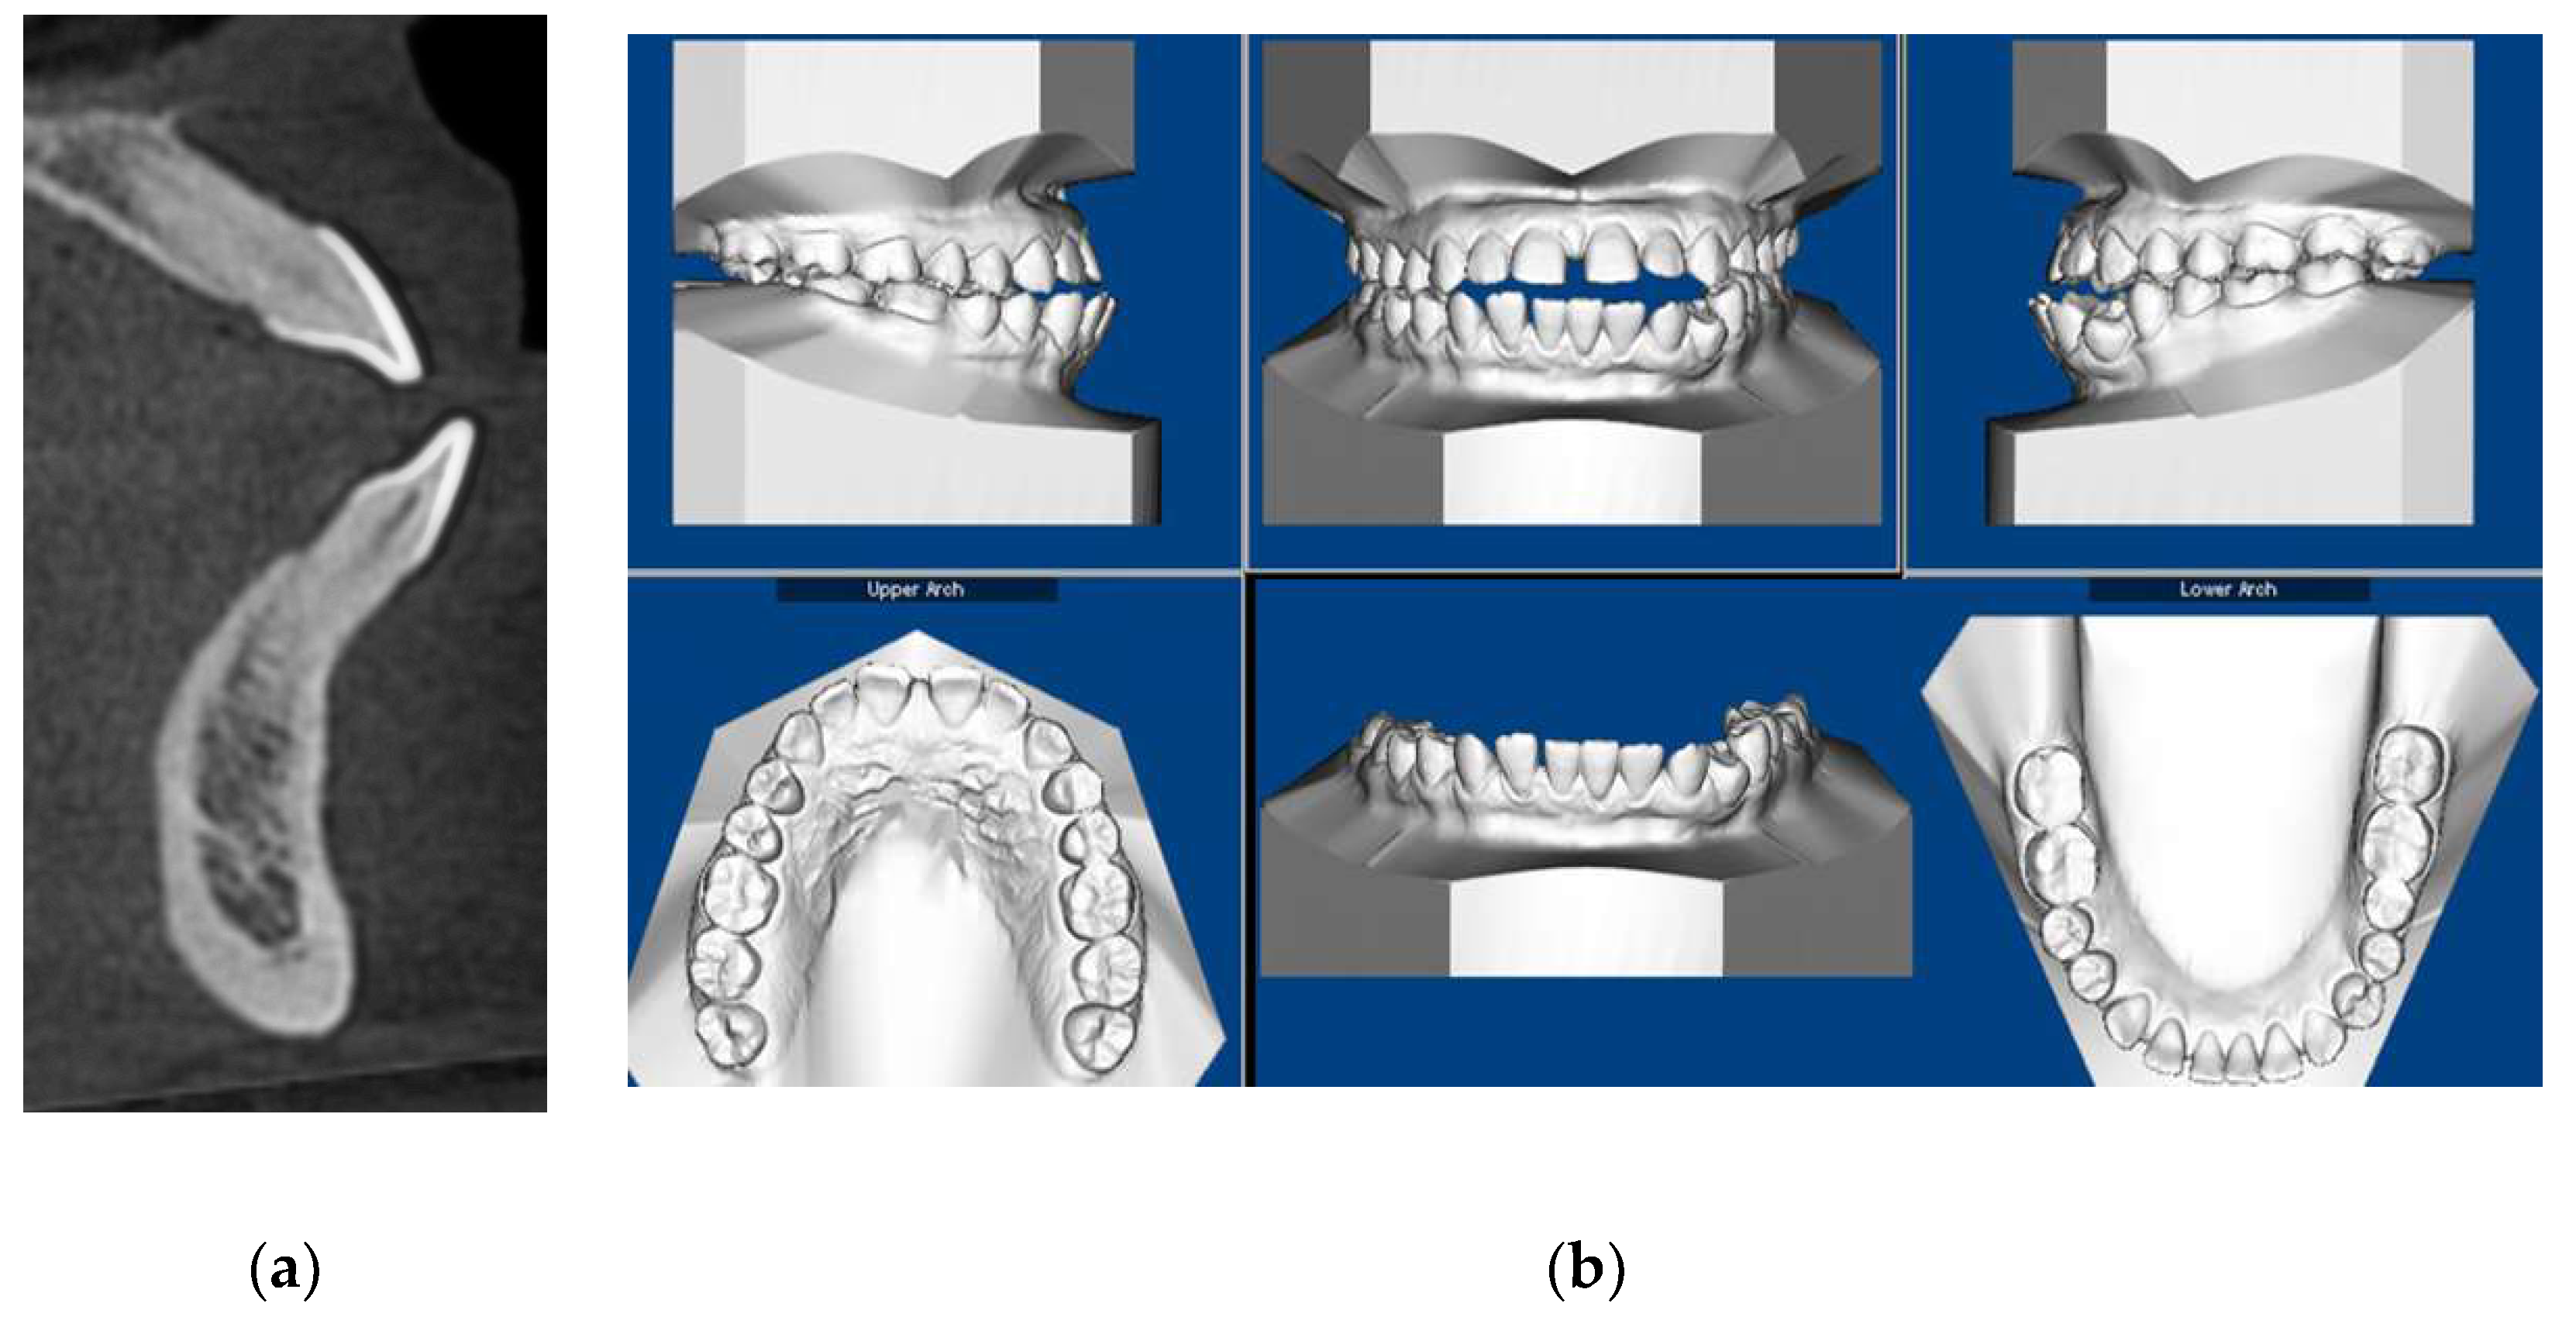

3.1. Clinical Records

3.2. CBCT-Driven Radiographs

3.2.2. Panoramic and Sagittal Screen Radiographs